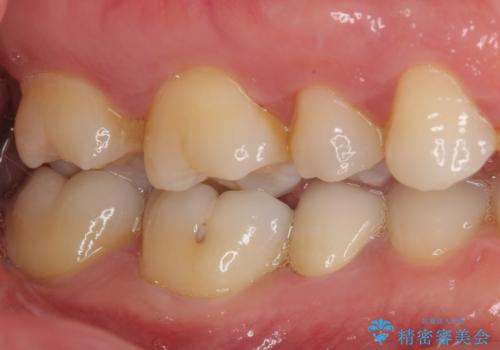

患者様と相談の上、再根管治療を行い、その後オールセラミッククラウンにて補綴治療を行うこととしました。

痛みが続く場合には、次の一手として歯根端切除術にて対応することを説明した上で治療を開始しました。

根管治療後9ヶ月で撮影したレントゲン写真より、歯根周辺の透過像が十分に消失している様子が認められました。